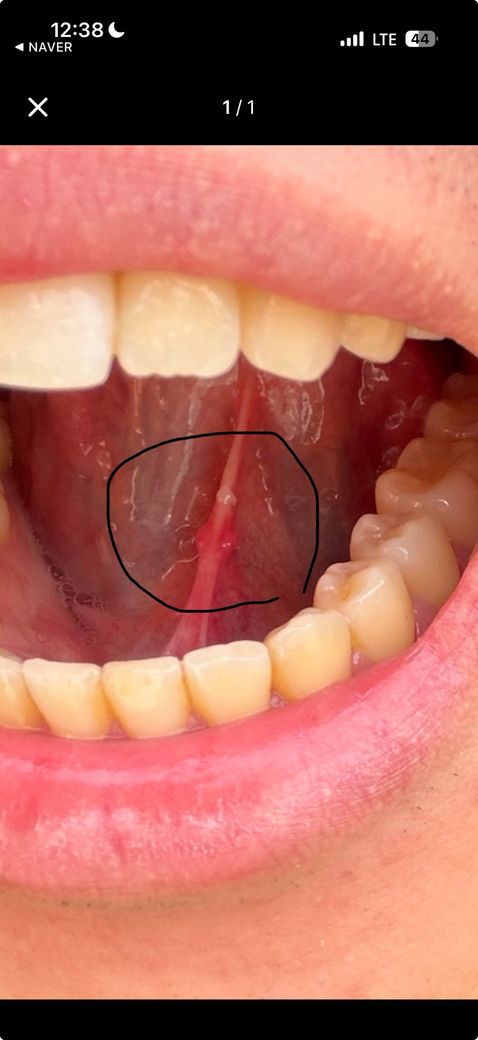

설 소대 옆 물집 인지 아닌지 궁금합니다

최근 혀 밑 설소대 주변에

양옆으로 봉긋한 병변 두 개와 가운데 헌 듯한 붉은 자국이 보여 상담드리고 싶습니다.

물집인지, 단순 자극이나 염증인지 궁금합니다.

최근 피로한 상태였고,

며칠 전 구강 성접촉(구강설교)이 있었던 점도 관련이 있을지 확인 부탁드립니다. 상세한 설명 해주시면 감사하겠습니다.

사진과 설명을 종합하면, 보이는 병변은 전형적인 “물집”보다는 설소대 주변 점막의 국소 자극성 염증 또는 경미한 외상성 병변 가능성이 더 높아 보입니다.

사진상 가운데 붉은 부위는 설소대 바로 옆 점막에 얕게 헌 듯한 미란(표재성 점막 손상) 형태이고, 양옆의 봉긋한 구조는 투명한 액체가 차 있는 수포라기보다는 정상 점막이 부어 보이거나 소타액선이 일시적으로 도드라져 보이는 양상에 가깝습니다. 실제 물집이라면 맑은 액체가 비쳐 보이거나 쉽게 터진 흔적이 동반되는 경우가 많습니다.